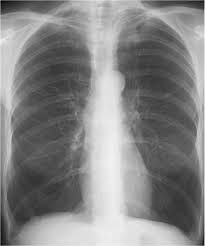

Meaning of lung hyperlucent.

Hyperlucency x ray definition. The obstruction that leads to lobar emphysema typically causes dynamic hyperinflation which manifests radiographically as lobar hyperlucency and mediastinal shift on the chest x ray. Spirometery of the patient was within normal limits. Even in adults pulmonary hyperlucency can be caused by congenital and acquired conditions. Information and translations of lung hyperlucent in the most comprehensive dictionary definitions resource on the web.

Abstract pneumothorax is the most urgent cause of a hyperlucent thorax. The radiographic finding that a lung or portion thereof is less dense than normal as from air trapping by a bronchial foreign body asymmetric emphysema or decreasing blood flow. Emphysema causes both over inflation and decreased pulmonary vasculature. Asymmetrical distance between the medial.

An x ray simply is fundamentally useless to properly diagnose your problem. A rotated posterior anterior view may result in artifactual decreased attenuation on the side rotated anteriorly because of a shorter distance between the patient and the incident x ray beam. Hyperlucency imaging a region on a plain film with tissue density allowing for transmission of x rays. Initial interpretation should include excluding pseudo causes of hyperlucency because of technical factors.

Spirometery of the patient was within normal limits. The most common causes of pulmonary hyperlucency in adults are summarized in figure 1. Hyperlucent lungs result from air trapping or decreased pulmonary vasculature. Unilateral hyperlucent lung.

Contrast enhanced computed tomograph cect of the chest showed an unremarkable lung fields and vasculature. An understanding of the broad differential di agnosis of pulmonary hyperlucency is necessary to determine the underlying cause and provide appropriate patient care. Every unnecessary x ray in a woman of child bearing age represents a danger that should be weighed against the benefits. What does lung hyperlucent mean.